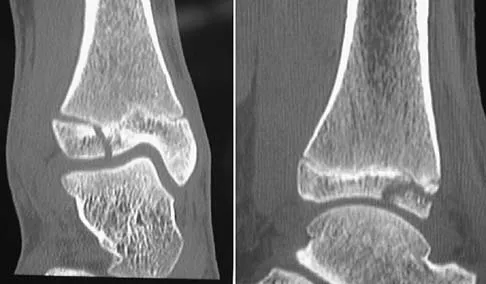

A 13-year-old girl injures her ankle playing soccer. Radiographs reveal a displaced Tillaux fracture. CT scans are shown in Figure 25. What is the most important consideration for appropriate management?

Detailed Explanation